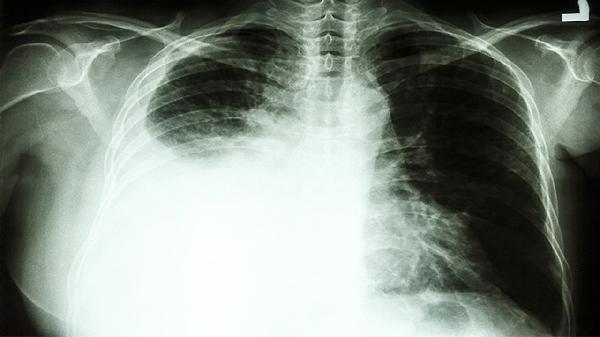

靶向药与中药联用需间隔2小时以上服用,避免影响药物吸收。含圣约翰草等成分的中药可能降低靶向药疗效,含黄酮类中药可能增加药物毒性。治疗期间需定期复查CT评估疗效,监测血常规和肝肾功能变化。